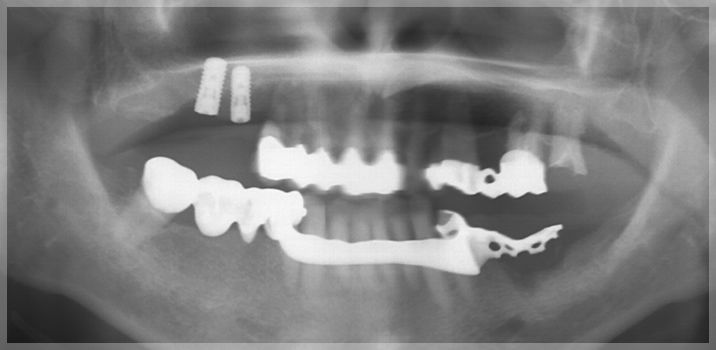

初診時

右上6、7 インプラント埋入

このような場合、歯が失われたままの右上の奥歯のように治療期間がかかる部位や奥歯での噛み合わせを早期に作ることから着手します。今回の場合はインプラント治療を行っています。

右上4相当部GBR

インプラントは骨に支えられることで機能します。しかしインプラントを支えるだけの骨が残っていない場合もあります。そのような場合骨を造成する処置を行うことでインプラント治療をすることが可能になります。

今回の場合でも骨を造成する処置を行っております。この処置においても麻酔をしっかりとするので痛みを感じることなく処置が行えます。骨が作られるまでの間3ヶ月ほど待機することになりますので早期に処置を行うことで治療期間を短縮することができます。